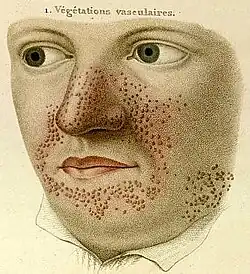

Hautveränderungen

Hautveränderungen kommen in unterschiedlicher Ausprägung vor und treten zum Teil altersabhängig auf. Erste Hautveränderungen sind harmlose Pigmentstörungen, weiße blattförmige Flecken am Körper (so genannte ash-leaf spots) und kommen bei über 80 % der Patienten bereits im ersten Lebensjahr vor. Ihre Erkennung wird durch die Wood-Lampe erleichtert. Im späteren Kindesalter treten typischerweise symmetrisch im Bereich beider Nasolabialfalten gelegene rötliche Papeln hinzu. Hierbei handelt es sich um Angiofibrome, gutartige Hamartome die in Traité théorique et pratique des maladies de la peau (Paris 1826–1827, 1835) von Pierre François Olive Rayer erstmals[8] und von John James Pringle 1890 erstmals als Adenoma sebaceum beschrieben wurden.[9] Typisch sind auch leicht erhabene lederartig verfestigte lumbosakrale Hautläsionen, die als „shagreen patch“ bezeichnet werden (bis zu 40 %). Vom Nagelfalz ausgehende derbe, rötliche fibromatöse Knoten werden als Koenen-Tumor bezeichnet und treten bei 22 % der Patienten in der späten Kindheit auf.[10]